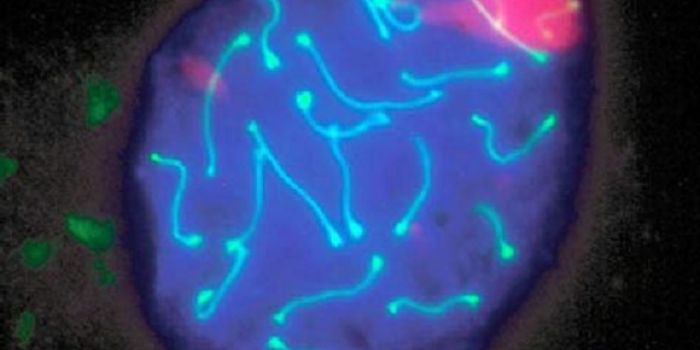

APR 28, 2022Genetics & GenomicsLupus is an autoimmune disease that can impact anyone, but tends to affects women between the ages of 15 and 45. The dis ...